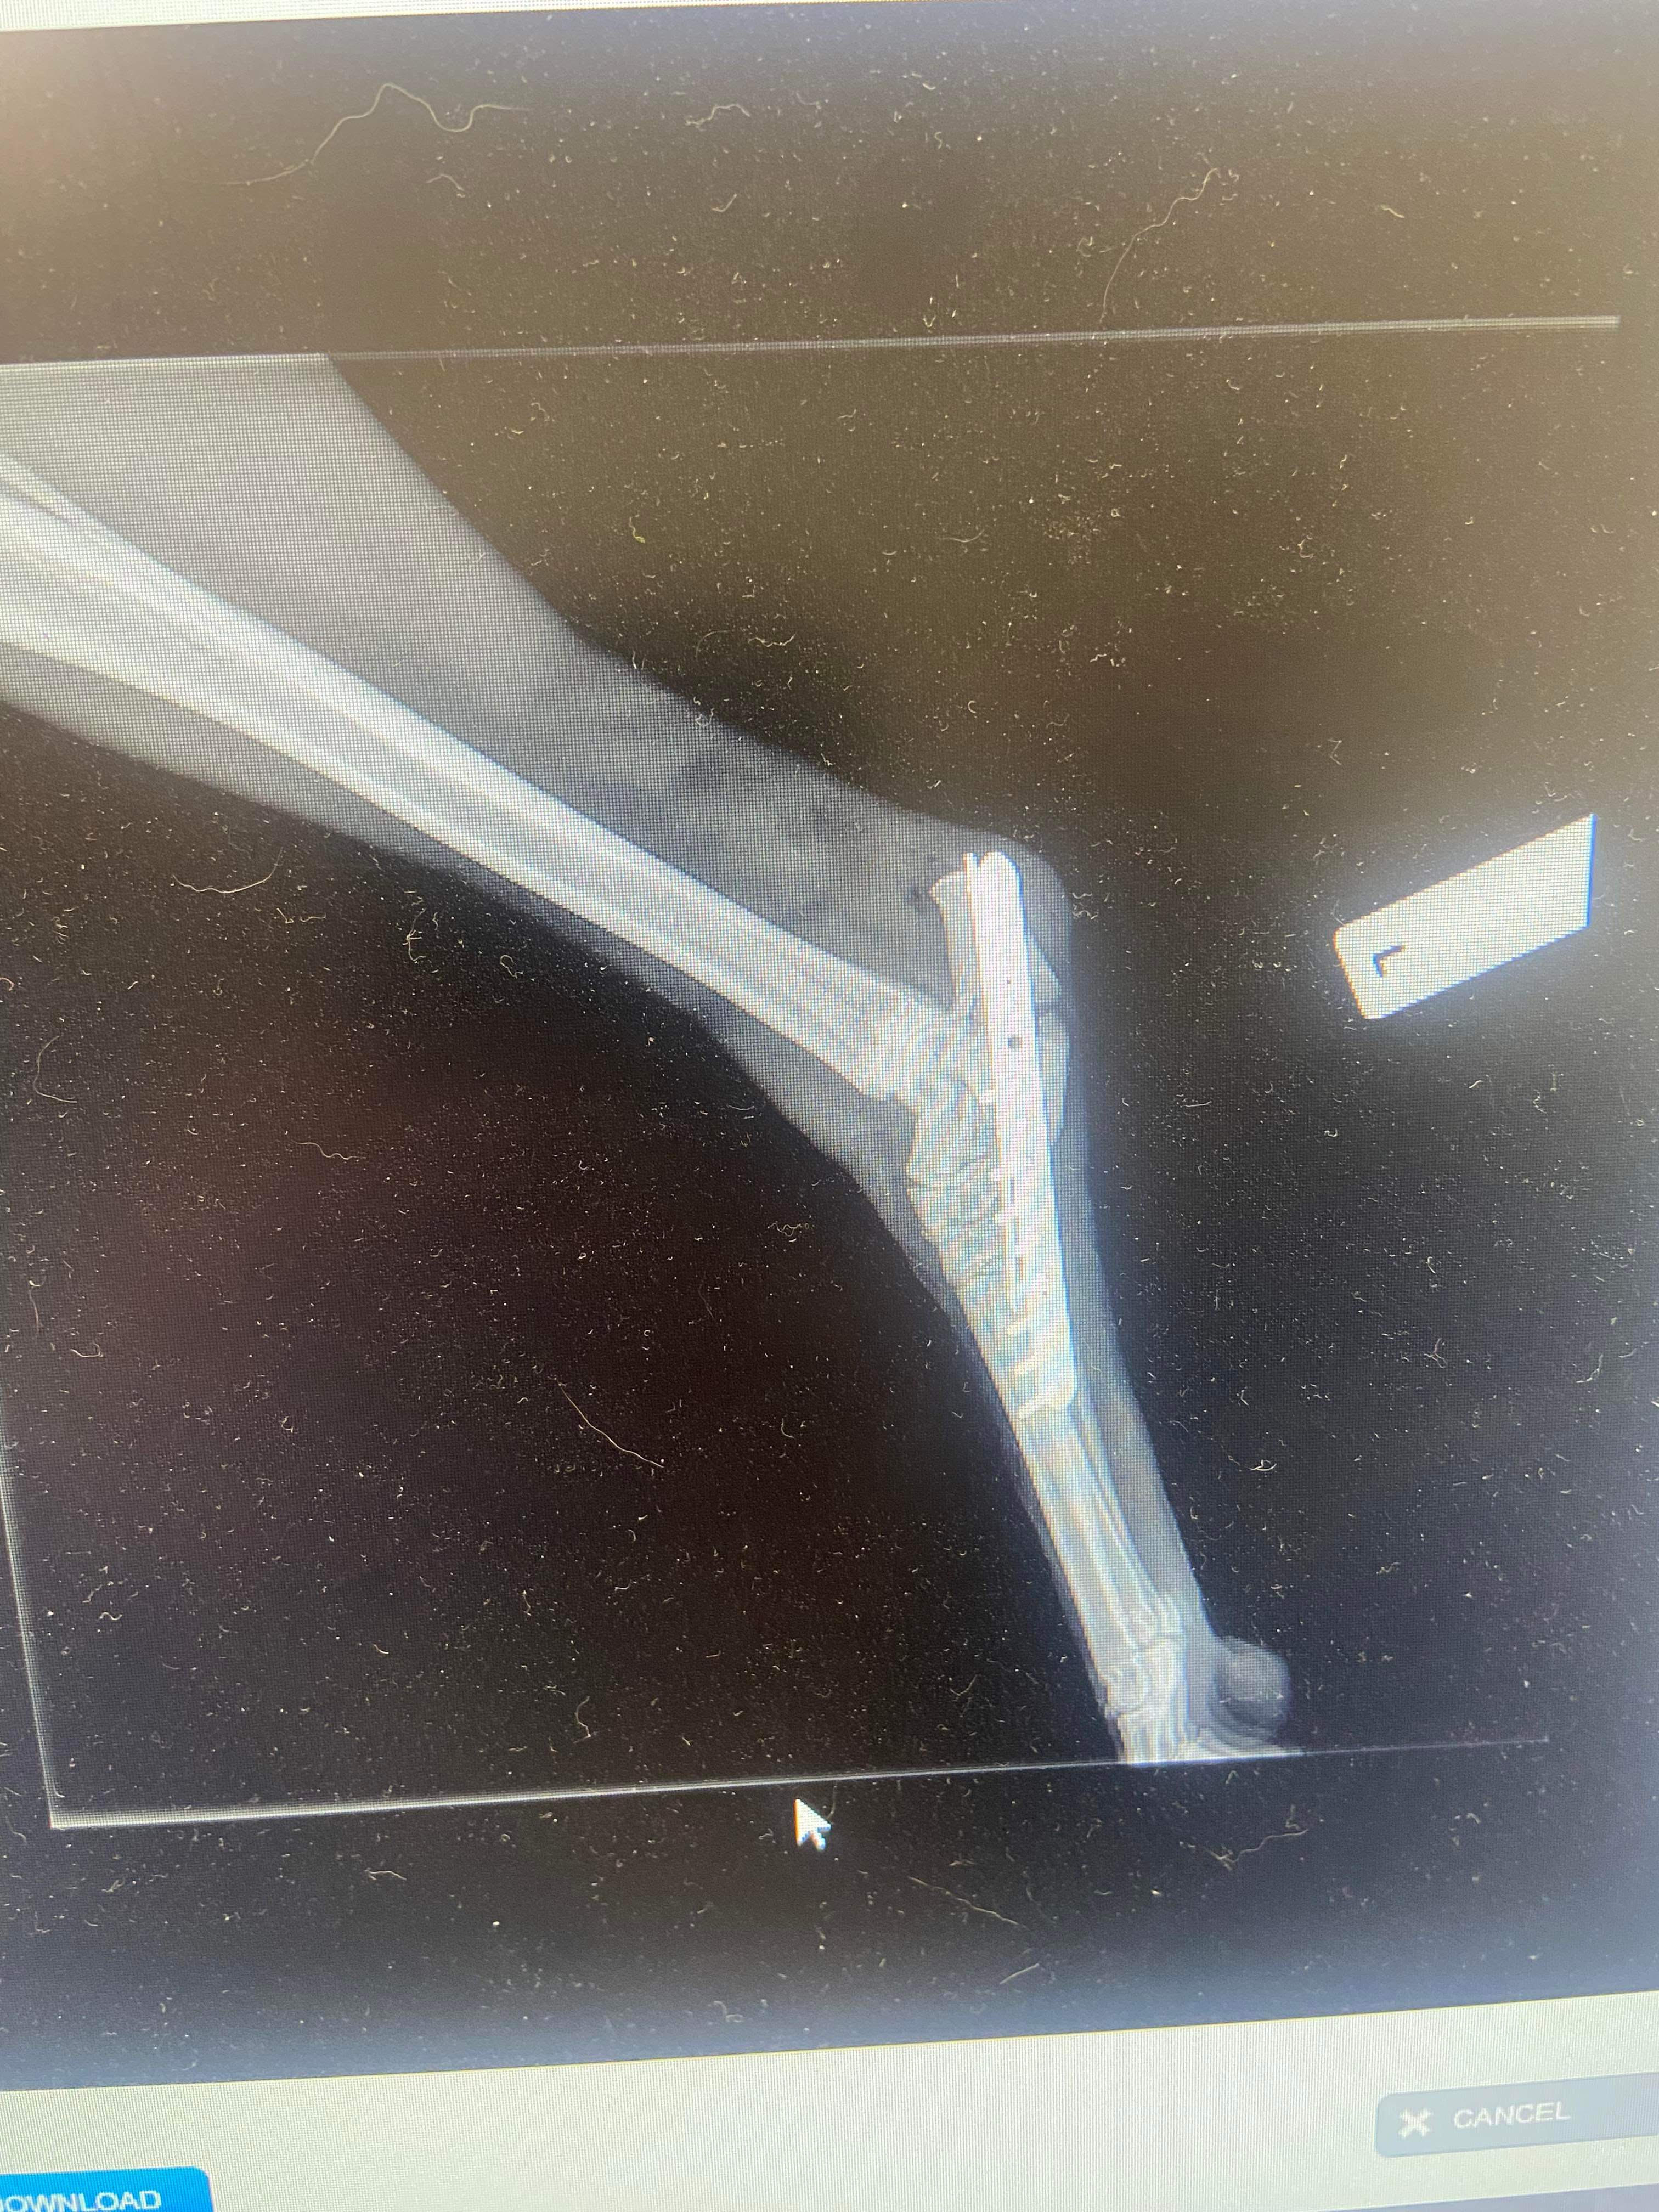

This accident resulted in a broken bone around his carpal joint, which connects to his achilles. Patrick required urgent surgery to rectify this.

On 18th September Patrick's surgery took place while we all held our breath.